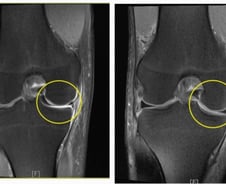

#. 서울 강북구에 사는 김모 씨(49세)는 얼마 전 봄을 만끽하려 산을 오르던 중, 가볍게 넘어져 무릎을 다쳤다. '괜찮겠지' 하는 심정으로 집에서 찜질하며 쉬었지만, 통증이 가라앉지 않아 병원을 찾았다. 문진 후 영상 검사를 받은 김 씨의 진단명은 '반월상 연골 파열'. 무릎을 굽히고 펴는 동작이 불편하고, 통증이 심해 잠을 제대로 이룰 수 없던 김 씨는 반월상 연골판이 찢어져 있고 손상 부위가 커서 결국 수술받았다. 다소 생소한 이름의 반월상(반달 모양) 연골판은 허벅지 뼈와 정강이뼈 사이를 잇는 무릎 조직으로, 충격을 흡수할 뿐 아니라 연골의 접촉면을 넓혀 관절을 잘 움직이게 하는 역할을 한다. 스포츠 외상, 사고처럼 큰 충격을 받으면 손상당할 수 있다. 찢어진 연골판 조각이 관절 사이 껴 관절의 움직임을 방해하고 통증과 함께 무릎이 굽혀지지도 펴지지도 않는 잠김 현상이 나타나 환자들이 불편함을 크게 느끼기도 한다. 초기에는 무릎의 힘이 빠지는 느낌과 함께 쪼그려 앉았다가 일